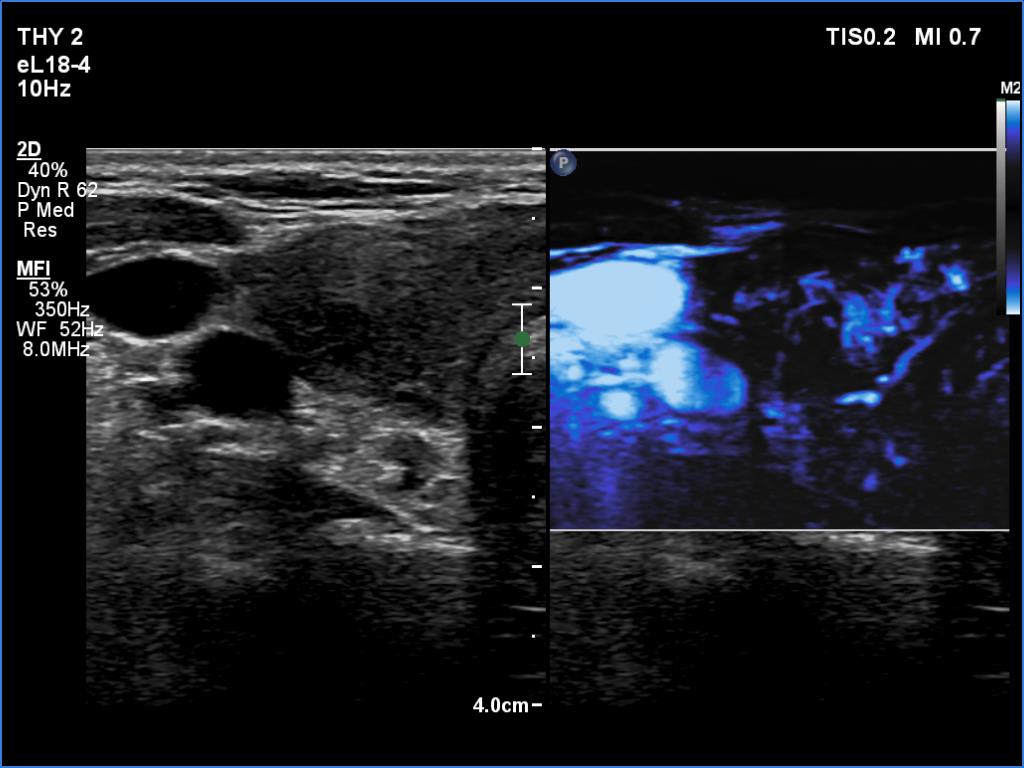

Right lobe, longitudinal scan

Right lobe, transverse scan, microflow imaging. The lobe is not avascular.